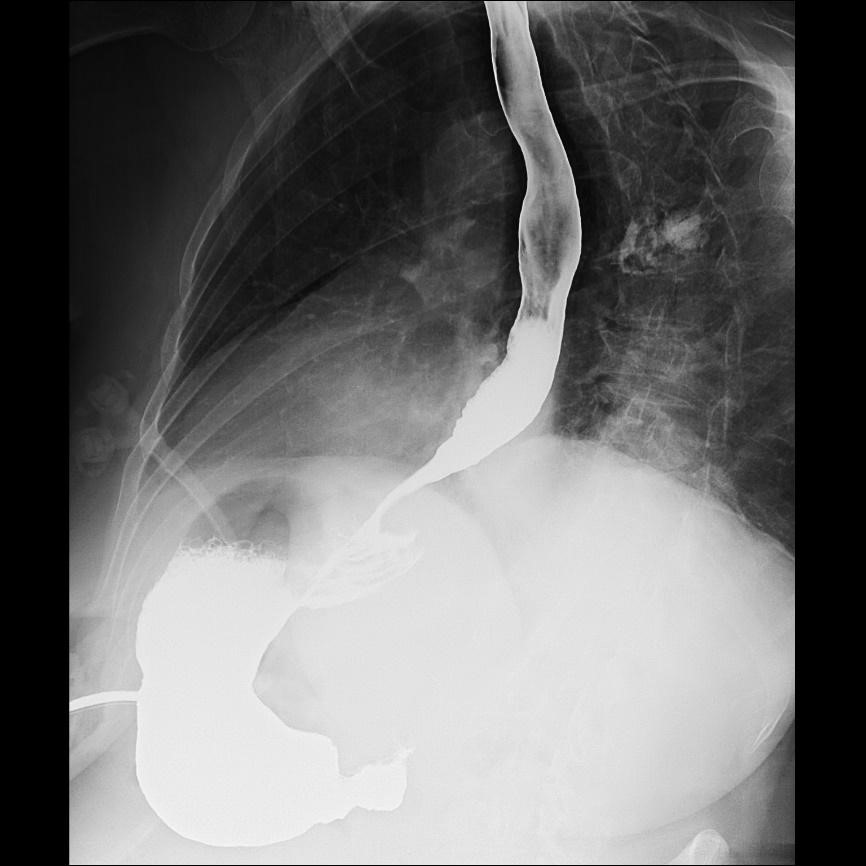

A la exploración, abdomen no doloroso y sin signos de irritación peritoneal. En la radiografía de tórax se observa imagen de hernia hiatal a nivel del tórax con nivel hidroaéreo (imagen 1). Se realiza gastroscopia informada de posible volvulación a nivel subcardial. En TC se observa dilatación sacular y focal de la región subcardial gástrica por encima del diafragma, con imagen de miga de pan y moderada cantidad de líquido libre, ausencia de restos alimentarios significativos en esófago distal y resto del estómago y sin signos de perforación de víscera hueca, hallazgos compatibles con volvulación subcardial. Se solicita tránsito esofagogástrico que es informado de recidiva herniaria sin afectación de la motilidad (imagen 2).

La paciente evoluciona favorablemente, tolerando dieta semiblanda y sin alteraciones significativas en el tránsito digestivo previo al alta (imagen 5).

Imagen 2. Tránsito esofagogástrico en el que se observa recidiva de hernia paraesofágica precoz tras funduplicatura de Nissen laparoscópica.

Imagen 5. Tránsito esofagogástrico tras plastia hiatal y gastropexia con sonda PEG.